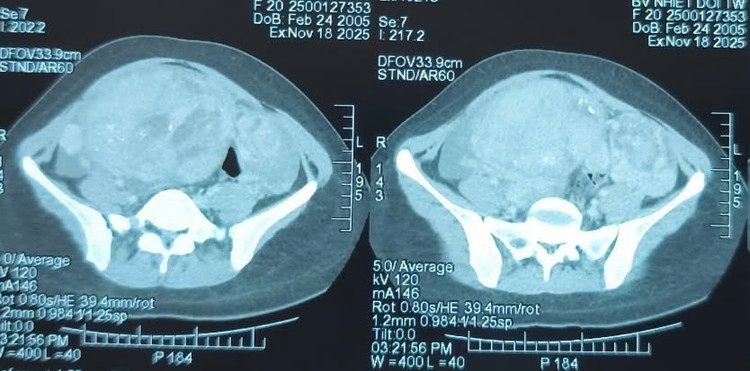

Khối u khổng lồ trên phim chụp - Ảnh BVCC

Khám lâm sàng ghi nhận một khối bất thường lớn vùng hạ vị. Hình ảnh chụp cắt lớp vi tính cho thấy khối u vùng hạ vị kích thước 110x163x244 mm, bờ không đều, bên trong có nốt vôi hóa và dịch tự do ổ bụng. Bệnh nhân được chỉ định phẫu thuật cắt bỏ khối u.